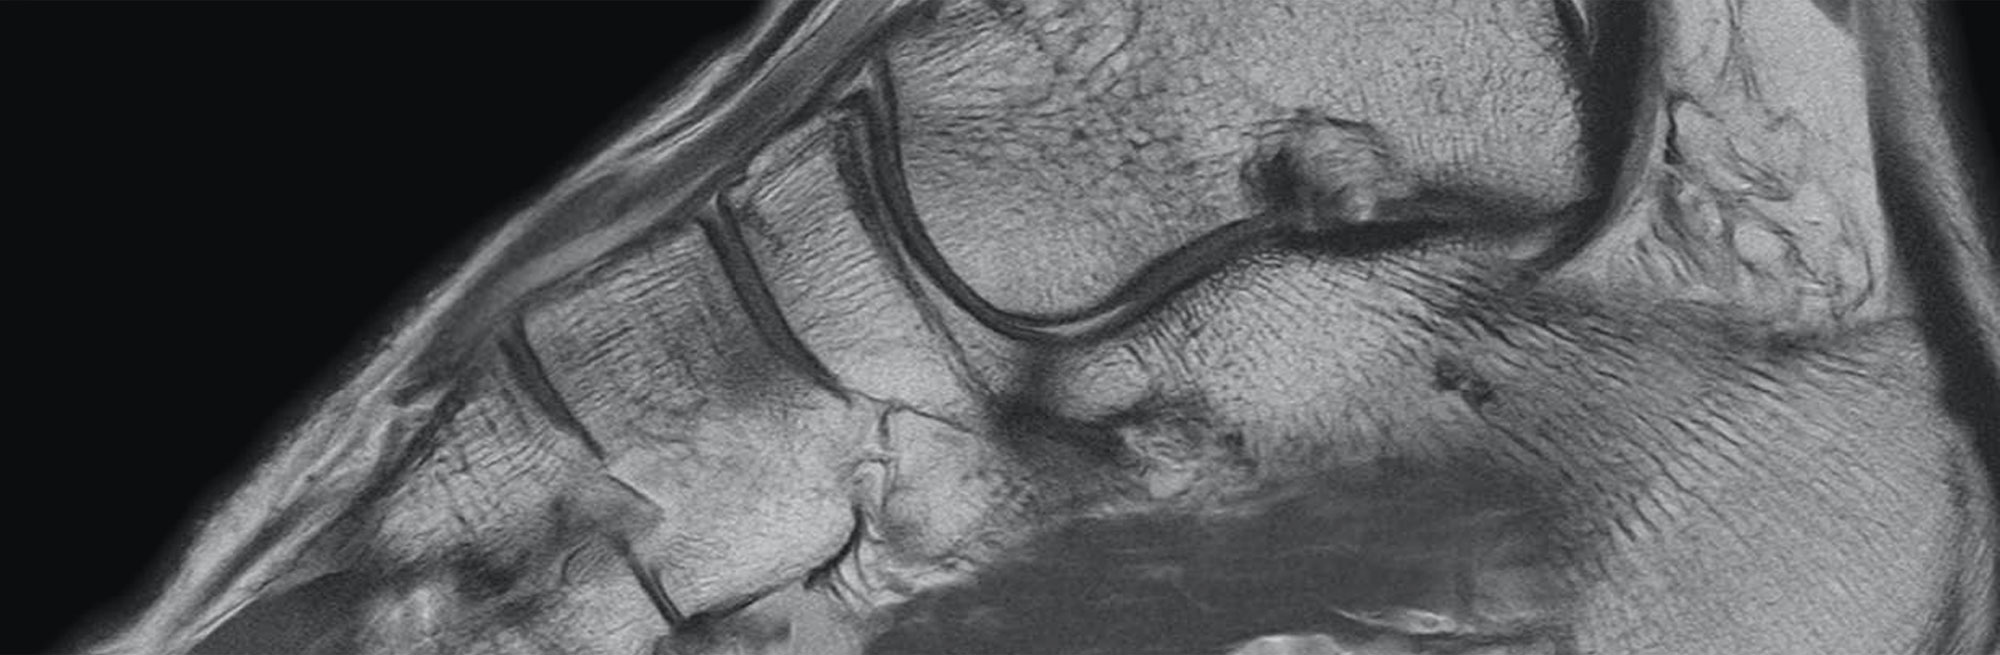

Wrist Conventional

Conventional coronal fluid sensitive sequence of the wrist shows intermediate signal of articular cartilage, and low signal in the triangular fibrocartilage (TFC).

Wrist UTE

UTE sequence of the wrist shows bright signal in the deep and calcified layer of cartilage (arrow) and in the triangular fibrocartilage (arrowhead) (TFC).